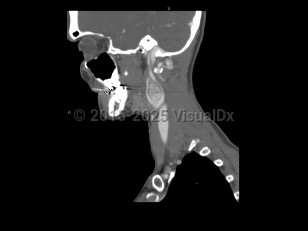

Peritonsillar abscessPeritonsillar abscess